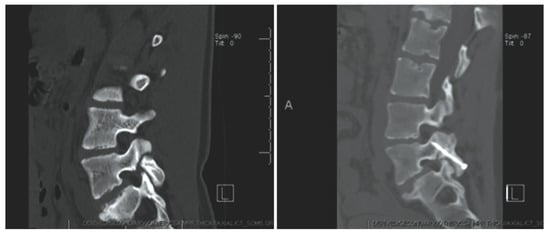

Levi Technique—Minimally Invasive Direct Pars Screw Placement

- Widi, G.A.; Williams, S.K.; Levi, A.D. Minimally invasive direct repair of bilateral lumbar spine pars defects in athletes. Case Rep. Med. 2013, 2013, 659078. [Google Scholar] [CrossRef]

- Ghobrial, G.M.; Crandall, K.M.; Lau, A.; Williams, S.K.; Levi, A.D. Minimally invasive direct pars repair with cannulated screws and recombinant human bone morphogenetic protein: Case series and review of the literature. Neurosurg. Focus 2017, 43, E6. [Google Scholar] [CrossRef] [PubMed]